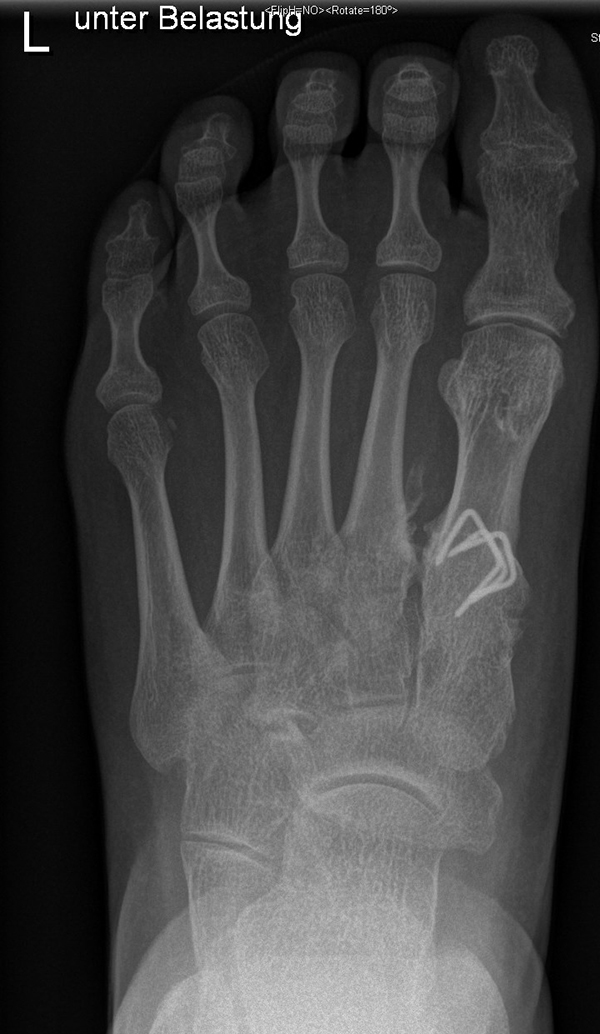

Damit die minimalinvasive Fußchirurgie zur Korrektur kindlicher oder jugendlicher Fußdeformitäten erfolgreich angewendet werden kann, erfordert die präoperative Diagnostik Röntgenbilder in drei Ebenen am stehenden Fuß. Röntgenbilder ohne Belastung des Fußes sind nicht zielführend. Im Fall von schweren Rückfußdeformitäten wird das obere Sprunggelenk in die radiologische Diagnostik mit einbezogen in Kombination mit der Rückfußaufnahme unter Belastung („Saltzman View“). Das OSG wird in zwei Ebenen geröntgt. Die streng seitliche Aufnahme des OSG kann bei den komplexen Fußdeformitäten mit der seitlichen Aufnahme des Fußes unter Belastung kombiniert werden. Das reduziert die diagnostische Strahlenbelastung der Kinder.

Indikationen für die beschriebenen Röntgenaufnahmen sind Klumpfußdeformitäten zur Beurteilung eines „flat top talus“ oder neurologische Grunderkrankungen mit varischer Fersenstellung wie zum Beispiel bei HSMN (Hereditäre Sensorische Motorische Neuropathie).